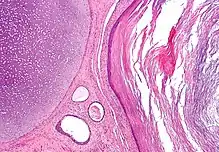

A mature teratoma is a grade 0 teratoma. They are highly variable in form and histology, and may be solid, cystic, or a combination of the two. A mature teratoma often contains several different types of tissue such as skin, muscle, and bone. Skin may surround a cyst and grow abundant hair (see dermoid cyst). Mature teratomas generally are benign, with 0.17-2% of mature cystic teratomas becoming malignant.[16]

Dermoid cyst

A dermoid cyst is a mature cystic teratoma containing hair (sometimes very abundant) and other structures characteristic of normal skin and other tissues derived from the ectoderm. The term is most often applied to teratoma on the skull sutures and in the ovaries of females.